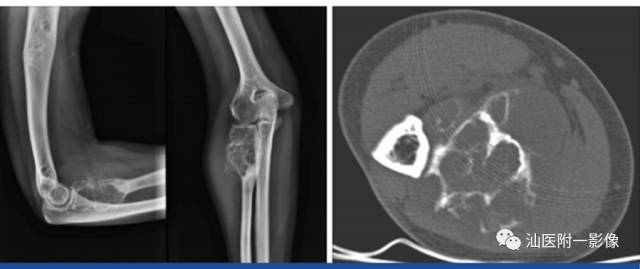

1.骨软骨瘤

•又称骨软骨性外生骨疣,特征为位于骨外表面的有软骨帽的骨性凸起。

•最常见的良性骨肿瘤(20-25%)。10-30岁多见。

•好发于长骨的干骺端(膝关节周围、肱骨近端)。

•病理:骨性基底+软骨帽+纤维包膜。